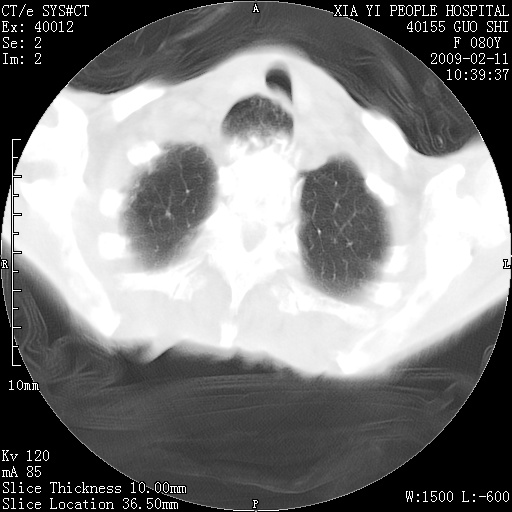

以下是引用随光逐影在2009-2-16 16:34:00的发言:[br]1)考虑右前纵隔皮样囊肿。2)双侧少量胸腔积液。

以下是引用zjzjr在2009-2-16 17:30:00的发言:[br]支持囊性畸胎瘤 双侧少量胸腔积液。